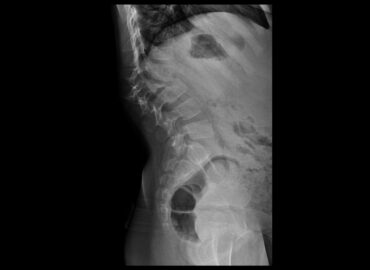

Paciente femenina de 25 años de edad. Ingresa por presentar masa dorsal gigante asociado a lesión cutánea hiperpigmentada y […]